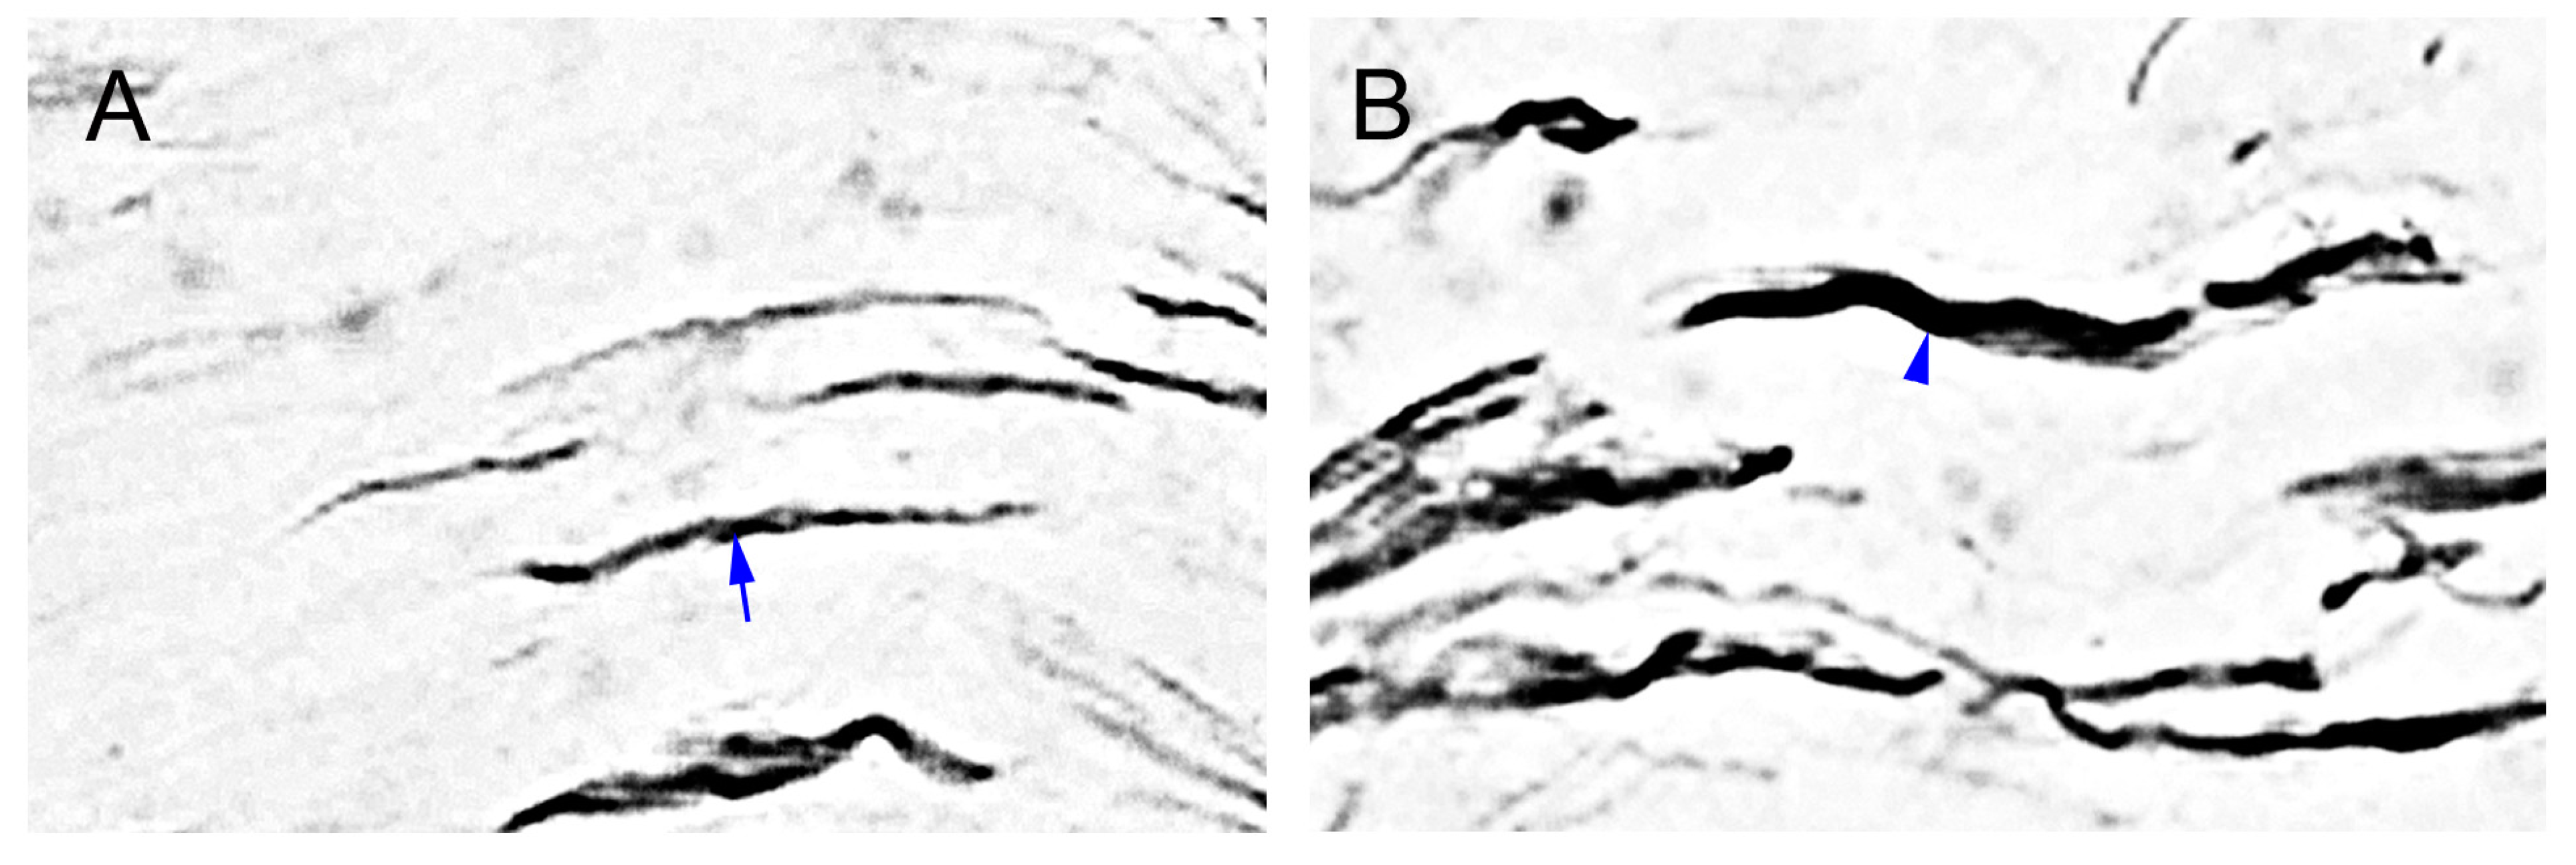

2.2. The Degeneration of Neurofilament 200 (NF-200)-Immunoreactive (IR) SENFs in Dermis after CCI

2.3. CCI-Induced the Significant Loss of Dermal Calcitonin Gene-Related Peptide (CGRP)-IR SENFs